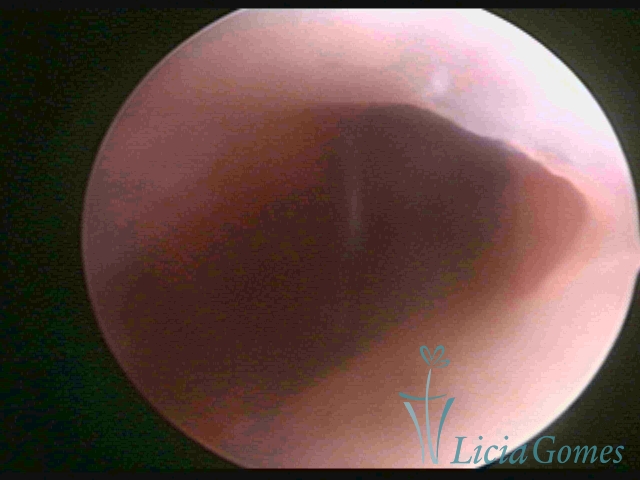

First part or proximal section or lower section:

During the proliferative phase, a light, crystalline mucus with a low adherence to the scope is found. The crypts and buds are a little swelled and vascularized, microvesicular, resembling grape clusters.